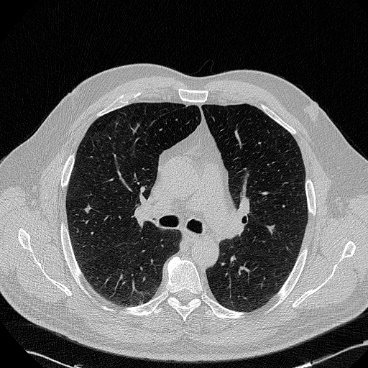

相关图片展示: